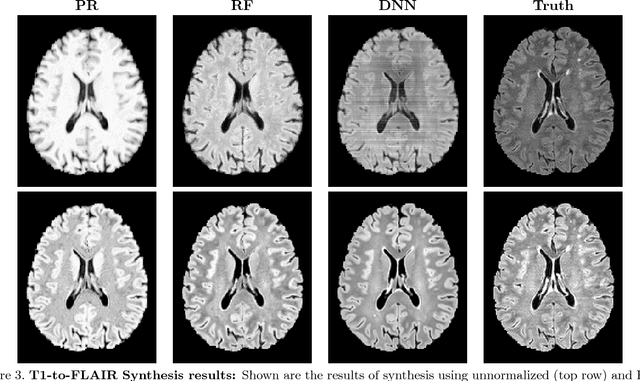

Image synthesis learns a transformation from the intensity features of an input image to yield a different tissue contrast of the output image. This process has been shown to have application in many medical image analysis tasks including imputation, registration, and segmentation. To carry out synthesis, the intensities of the input images are typically scaled--i.e., normalized--both in training to learn the transformation and in testing when applying the transformation, but it is not presently known what type of input scaling is optimal. In this paper, we consider seven different intensity normalization algorithms and three different synthesis methods to evaluate the impact of normalization. Our experiments demonstrate that intensity normalization as a preprocessing step improves the synthesis results across all investigated synthesis algorithms. Furthermore, we show evidence that suggests intensity normalization is vital for successful deep learning-based MR image synthesis.